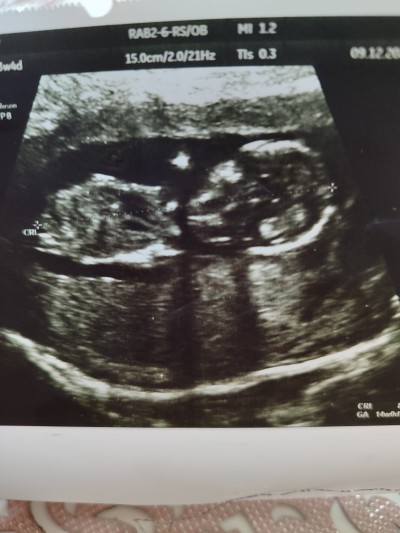

Merhabalar arkadaşlar ultrason görüntüsüne göre bebeğin cinsiyeti nedir bilgisi tecrübesi olan varsa tahmin de bulunur musunuz 13+4

image